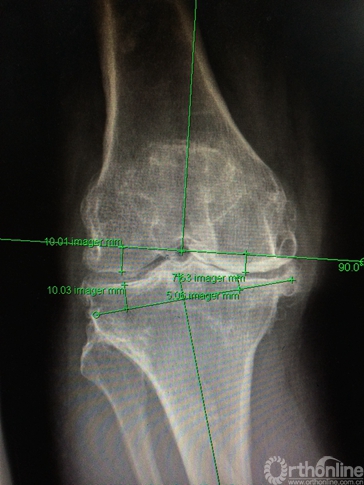

(2)畸形发生在冠状位,关节外股骨中下段;下肢全长片测量,股骨中下段内侧成角,股骨外翻角约14度(图1b);

术后常规进行抗凝、预防感染、镇痛处理,24小时拔除引流后关节伸屈功能锻炼,并扶拐下地负重。拍摄术后X片,下肢力线恢复,假体安放位置准确(见图5)。

图5. 术后全长片显示下肢力线恢复良好。